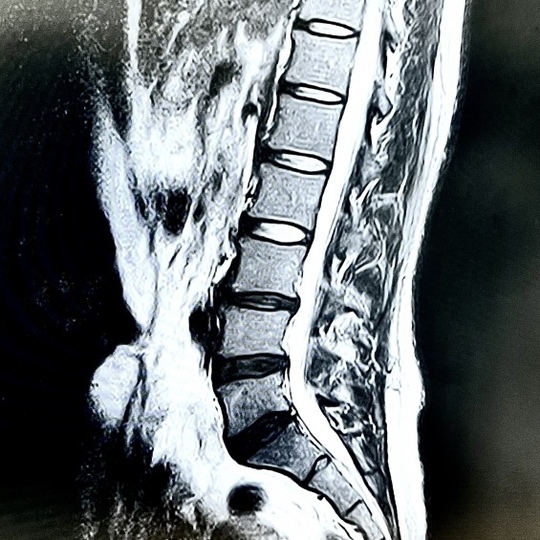

お客様の中には、当院にお越しになる前に病院(整形外科)に行き、レントゲンやMRIなどの画像をもとに、医師に診断されたのち、来院される方もいらっしゃいます。

実は、レントゲンやMRIなど画像に写った様々な変形と、お客様の腰の症状は一致しないことが多いです。

なので、大部分の人の変形は、腰の痛みとは関係のないただの変形、加齢現象としてそこに写りこんでいるだけです。(=偽性タイプ)

こういったバランスの部分は、レントゲンやMRIでは評価できないことです。